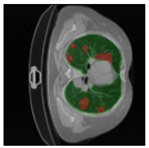

In Table 6, a comparison of the ground truth and prediction results of each model is presented in 2D, along with the 3D projection of each model. The visual analysis of the predictions provides additional insights into the performance of each model. The visualizations demonstrate that Attention UNet captures the intricate details of the lung construction more accurately, resulting in more precise segmentation of the infected areas compared to other models.

Table 6.

Comparison of ground truth and model prediction results using UNet, LinkNet, Attention UNet, UNet 3+, and TransUNet.

Mask preprocessing plays a crucial role in consolidating the left and right lung labels into a single mask for enhanced segmentation accuracy. The merging process involves equating the pixel values of the left lung mask and right lung mask, resulting in a unified lung mask that includes both lung regions. By incorporating this preprocessing step, the resulting lung and infection masks exhibit three distinct pixel values: 0 represents the background, 1 represents the lung, and 2 represents the infection. This merging process aims to assist the model in avoiding errors in distinguishing between the left and right lungs. The identification of the left lung and the right lung can be seen by projecting the prediction results of the model in 3D. The following in Table 3 is an example of a lung and infection mask before and after mask preprocessing.